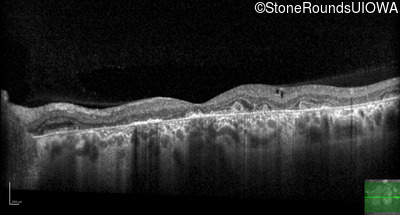

Optical Coherence Tomography - Right - 20/150

Exemplar / OCT Stack

Optical Coherence Tomography - Left - 20/70